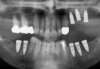

Cas 2: vues panoramiques

AVANT REHABILITATION

PENDANT REHABILITATION 3 SECTEURS MOLAIRES

APRES REHABILITATION 3 SECTEURS MOLAIRES